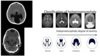

Q

what infection caused the finding?

A

prenatal CMV infection